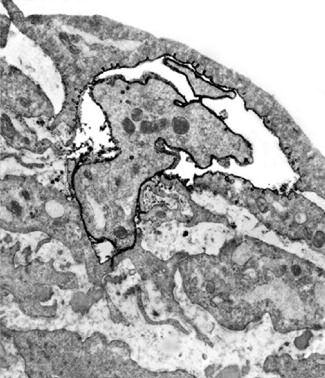

Nella figura A è possibile vedere la struttura del tessuto di un seno non predisposto per l’allattamento, caratterizzato dalla struttura densa di tessuto connettivo che circonda il condotto del latte, al centro dell'immagine, in gran parte chiuso.

In netto contrasto, la figura B mostra la struttura cellulare di un seno predisposto all’allattamento, caratterizzato da tessuto connettivo lasso, la presenza di cellule della ghiandola principale necessaria per la produzione di latte (piccoli cerchi bianchi), nonché il condotto del latte ampiamente aperto (al centro dell'immagine).

Immaginate la quantità di enzimi che digeriscono il collagene necessari per l'avvio di questo processo e l’affascinante progetto architettonico per ricostruire il tessuto mammario per ciascuna di queste fasi.

A. Condotto del latte (chiuso) nel tessuto del seno in condizioni normali

B. Condotto del latte (aperto) durante l’allattamento

A Ripresa di un condotto del latte al microscopio, sito in un seno non predisposto all’allattamento (chiuso)

B. In funzione dell’allattamento si ristruttura il tessuto mammario. Il condotto è aperto e il latte può uscire.